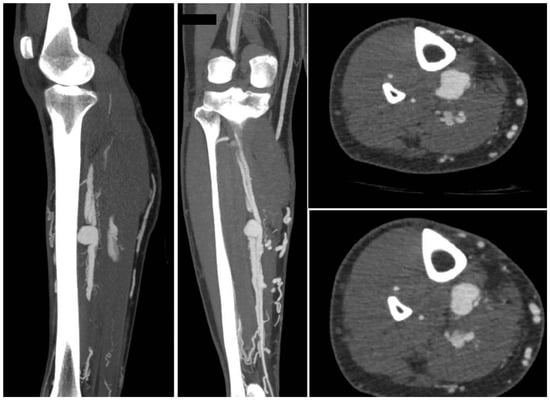

In light of a symptomatic aneurysm, treatment was offered to the patient. After discussing the risks of open and endovascular treatment options with the patient, an endovascular approach was opted for. The presence of a large aneurysm with an AV fistula and venous congestion posed an increased risk of significant bleeding complications associated with open surgery. An antegrade femoral access was obtained via a 5F sheath (Terumo, Shibuya-ku, Tokyo, Japan). After obtaining an angiogram, two coils were deployed in the aneurysm sac (Concerto PGLA helical PV-20-50-Helix and Concerto PGLA 3D PV-18-40-3D, Medtronic, Minneapolis, MN, USA), with the aim of causing sac thrombosis and obliterating the flows from multiple AV fistulas. As anticipated, this did not lead to complete occlusion of the aneurysm and AV fistula. A retrograde pedal access was obtained, and cannulation of the PTA was successfully performed with a V14 guidewire (Boston Scientific, Marlborough, MA, USA) (Figure 2 and Figure 3). After obtaining guidewire access, the aneurysm was excluded with a stent graft (Viabahn Endoprosthesis 5 mm × 50 mm, WL Gore, Flagstaff, AZ, USA). Immediately after the procedure, angiography control visualized complete exclusion of the pseudoaneurysm, occlusion of the sac, and absence of any AVF (Figure 4). Postoperatively, the patient reported pain reduction. Both pedal pulses were palpable. Postoperative antithrombotic therapy included aspirin 100 mg and clopidogrel 75 mg daily for 6 months. Additionally, Class 2 compression stockings were recommended for 1 month. After 18 months of follow-up, the patient was free of symptoms, and the stent graft was patent.

Figure 2.

(Left) to (right). An angiogram was obtained, and the aneurysm sack was coiled. Multiple attempts to cannulate the distal posterior tibial artery failed (A microcatheter is in the crural vein). After coiling the aneurysm sack, the AV fistula was still patent.

Figure 3.

(Left) to (right). Retrograde pedal access was obtained and cannulation was successful with a V14 Guidewire.